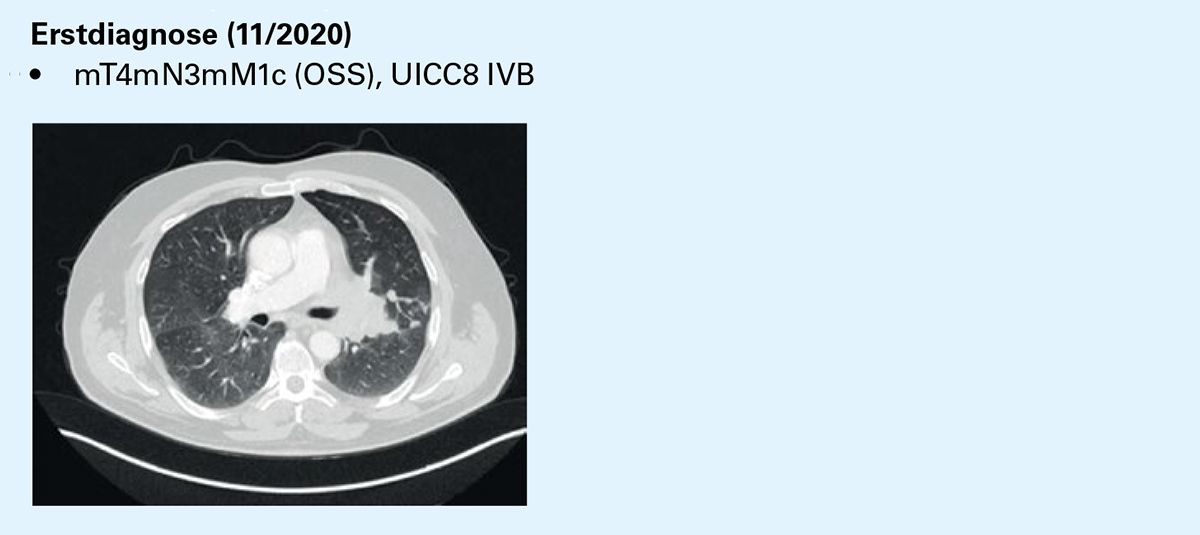

Erstdiagnose (11/2020)

• mT4mN3mM1c (OSS), UICC8 IVB